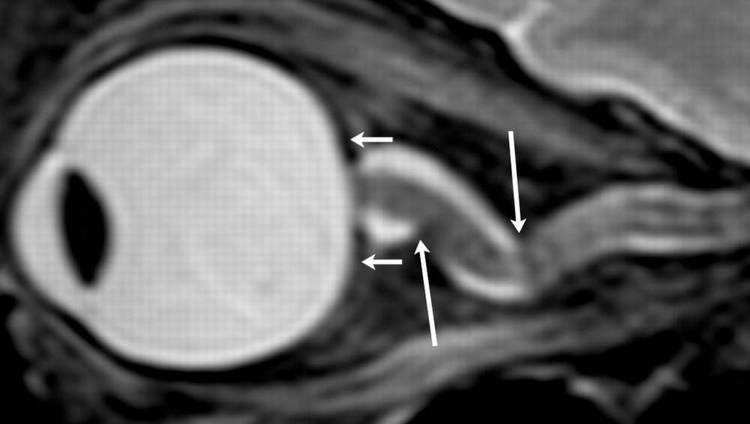

这个眼睛变平而且视觉神经被CSF弯曲。

相较于短时间任务的太空人,长时间任务的太空人眼睛的平坦度增加,而且眼球后方有较高含量的CSF。分析也显示,CSF含量越高,观察到的变形就越大。

艾伯林博士说:“这项研究提供有史以来第一次得自短期和长期任务太空人的定量证据,说明了在有视力损伤症候群(visual impairment syndrome)的太空人所看见的眼球变形,CSF所扮演的主要和直接角色。